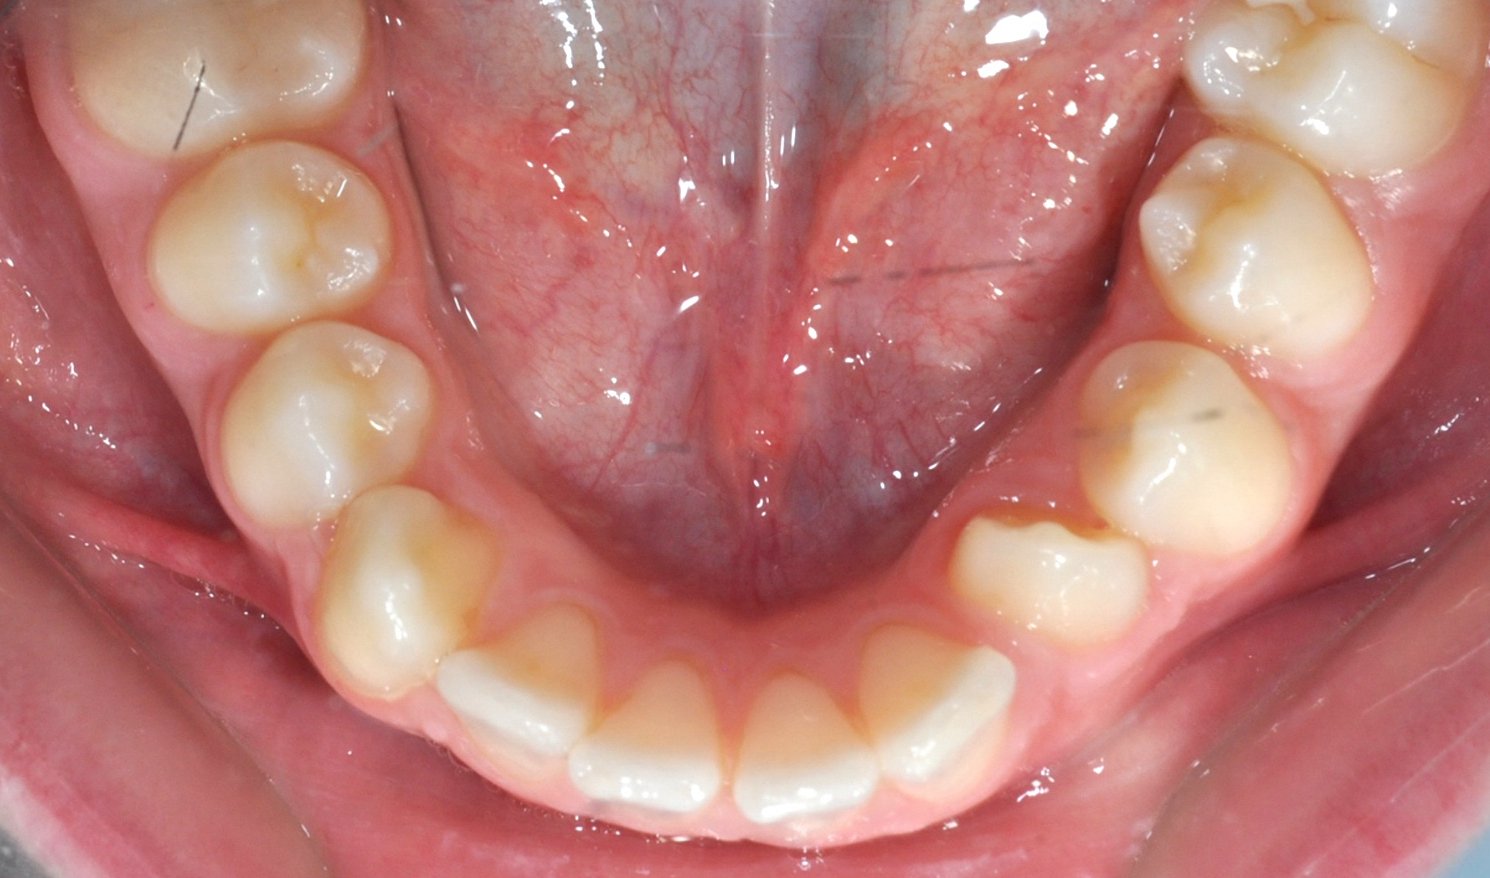

Paziente adulto con importante affollamento dei denti inferiori, arcate strette e tendenza al morso aperto, con difficoltà nel corretto contatto tra i denti superiori e inferiori.

Il trattamento con allineatori trasparenti ha permesso, in circa 18–20 mesi, di riallineare i denti, ampliare le arcate e migliorare la chiusura del morso, ottenendo un risultato stabile, funzionale ed esteticamente armonioso.

DOPO